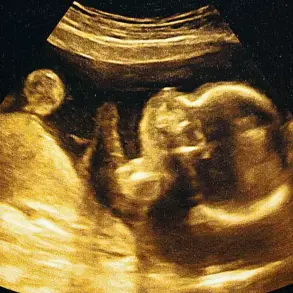

article image

A landmark study published in July in the journal *Nature Communications* has shed new light on the genetic underpinnings of autism.

Researchers modified mice to carry mutations in the *Shank3* gene, a mutation previously associated with ASD in humans.

These genetically altered mice underwent a series of behavioral tests designed to mimic social and exploratory interactions observed in rodents.

The results were striking: mice with *Shank3* mutations exhibited significantly reduced social behaviors, such as decreased exploration of their surroundings and minimal interaction with other mice.

This mirrors some of the social challenges seen in autistic individuals, offering a compelling model for further study.